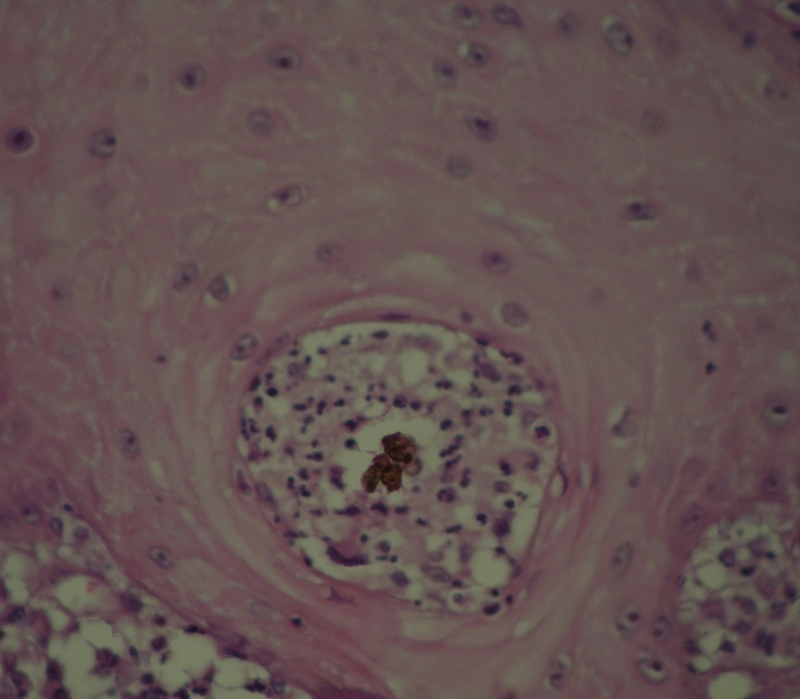

Since there are no pathognomonic signs or symptoms, diagnosis requires a set of laboratory investigations. In the first instance, biopsy of the affected area is required, looking for clustered muriform cells [10] (Figure 3). Microbiological culture must be used to determine the aetiological agent. Sabouraud-agar (SGA) is recommended; however, due to the nature of the fungus, culture can take at least a week to yeild results [2]. PCR is also recommended in order to provide molecular differentiation if the culture or microscopy was not conclusive [3].

Figure 3:Granular reaction with giant cells ingesting a muriform cell (H&E).